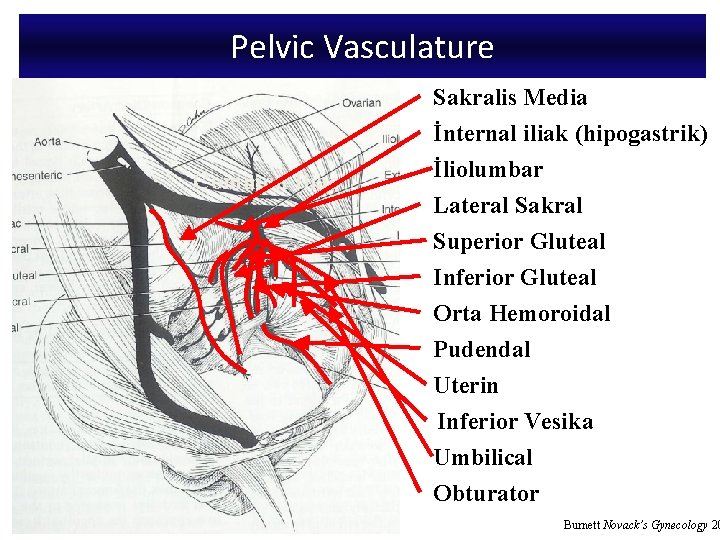

Pelvic Vasculature Sakralis Media İnternal iliak (hipogastrik) Common Iliac İliolumbar Lateral Sakral Superior Gluteal Inferior Gluteal Orta Hemoroidal Pudendal Uterin Inferior Vesika Umbilical Obturator Burnett Novack’s Gynecology 20

Branches of the Internal Iliac Artery Anterior Division Posterior Division Uterine Umbilical Uterine vesical Obturator Internal pudendal Inferior gluteal Middle vesical Middle rectal Vaginal Superior gluteal Lateral sacral Iliolumbar

Collateral Arterial Circulation of the Pelvis Primary Artery Aorta Ovarian artery Superior rectal artery (inferior mesenteric artery) Lumbar arteries Vertebral arteries Collateral Arteries Middle sacral artery Lateral sacral artery External Iliac Deep iliac circumflex artery Inferior epigastric artery Iliolumbar artery Superior gluteal artery Obturator artery Femoral Medial femoral circumflex artery Lateral femoral circumflex artery Obturator artery Inferior gluteal artery Superior gluteal artery Iliolumbar artery Uterine artery Middle rectal artery Inferior rectal artery (internal pudendal) Iliolumbar artery

• Ovarian arteries – Originate directly from the aorta, inferior to the renal arteries. – Most frequently identified at the IP ligament. • Ovarian veins: – Left ovarian vein drains into the left renal vein – Right ovarian vein drains directly into the inferior vena cava.

Pelvic Vasculature Sakralis Media İnternal iliak (hipogastrik) Common Iliac İliolumbar Lateral Sakral Superior Gluteal Inferior Gluteal Orta Hemoroidal Pudendal Uterin Inferior Vesika Umbilical Obturator Burnett Novack’s Gynecology 20